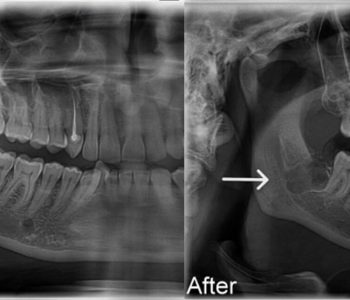

X-rays and evaluation to determine the best treatment approach.